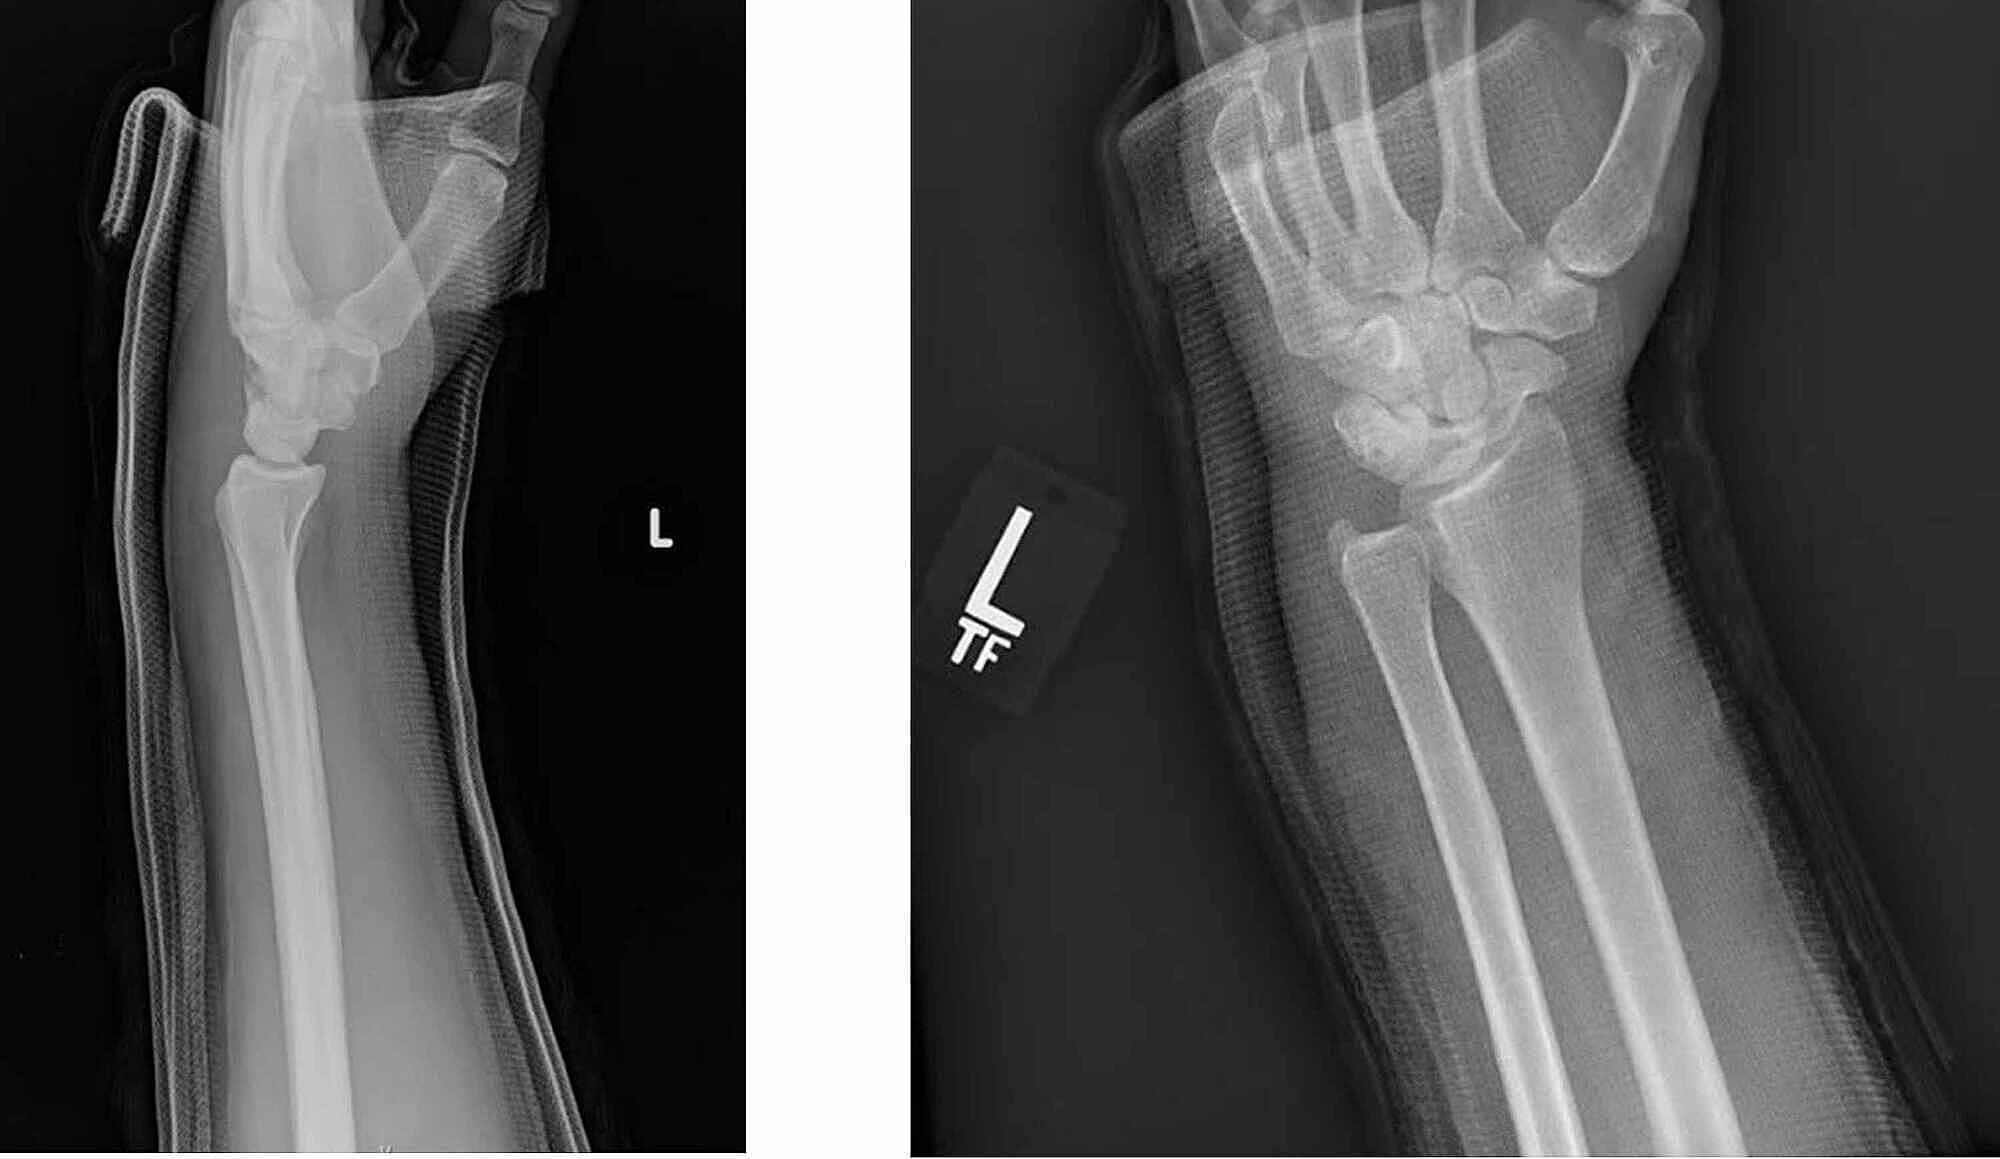

Xray images showing well reduced DRUJ without recurrent dislocation or How To Reduce Druj Dislocation We sought to review the clinical outcomes of conservative and operative treatment options for acute distal radioulnar joint (druj) instability associated with distal radius. By retracting the dislocated ulnar head, a limited view into druj is possible and this may suffice for removal of interposed soft tissue. A stable druj dislocation can be reduced and then put through an active. How To Reduce Druj Dislocation.